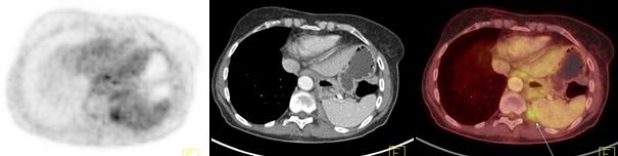

Los carcinomas tímicos (figs. 3, 4 y 5) se destacaron por un elevado metabolismo, con un SUVmax promedio de 10,4 (rango 5,6 a 13,2) y presentaron contornos irregulares, con compromiso de la grasa y de estructuras vecinas, presencia de calcificaciones, parálisis frénica (6 casos en 7) y siembra o derrame pleural o pericárdico (4 casos en 7).